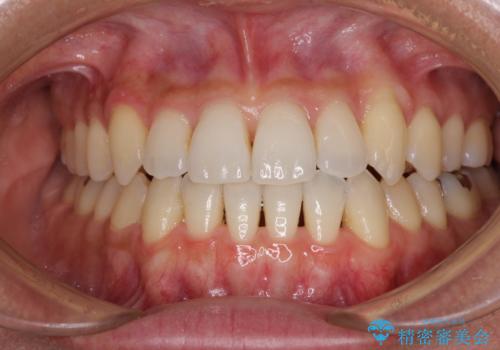

- 上下前歯のデコボコを気にして来院された患者様です。

写真より左側臼歯の咬合がタイトではないことが分かりますが、こちらは保定期間に徐々に咬合させていくこととしました。